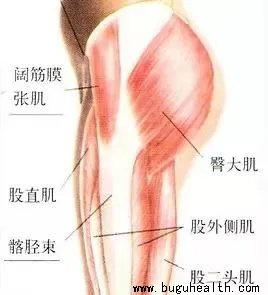

- 布骨医学科普:一个动作看出髋膝周围肌肉问题 布骨康复医疗中心 ,2021-11-16

- 久坐腰痛... 髋关节外侧弹响...膝盖外侧持续的疼痛...骨盆前倾、X或O型腿、外八字脚...这些有可能是髋周围或者腿上的一些肌肉变得紧绷而导致;在我们提出解决这些紧绷的肌肉之前,我们需要知道是谁?它是否真的紧?.....

- 最近几天,我们门诊先后接诊了几位髋关节弹响的患者,他们主要表现就是在做髋关节主动屈伸,活动的时候,会出现响声。大部分会出现咯噔的声音,听起来像肌肉或肌腱划过骨头的声音。在临床上,髋关节弹响是一种常见的病症,我们通常把髋关节弹响理解为髂胫束摩擦。.....